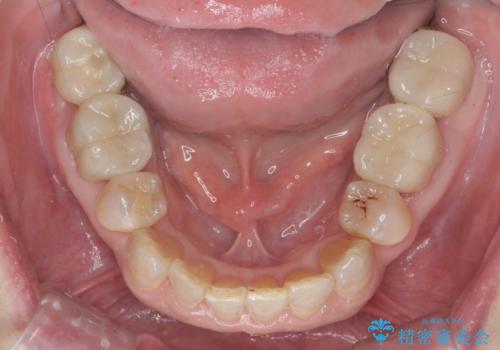

- 50代女性

- 1年6ヶ月

- ぐらぐらする歯や銀歯、なんとなくにおいのする奥歯の治療を求めて来院されました。

X線、歯周組織検査の結果、全体的に奥歯には重度〜中等度の歯周病の問題が見られました。

残すことのできない歯、予後の悪い歯を抜去し、ブリッジイ・ンプラントによる機能回復をおこなっていくと同時に、残すことのできる歯には歯周病治療をしっかりと行い、

将来に渡りしっかりと自分の歯で噛めるような口腔内環境を構築していきます。

においやぐらつきなどの深い症状がなくなり、しっかりと噛めるようになった!と喜んでいただくことができました。